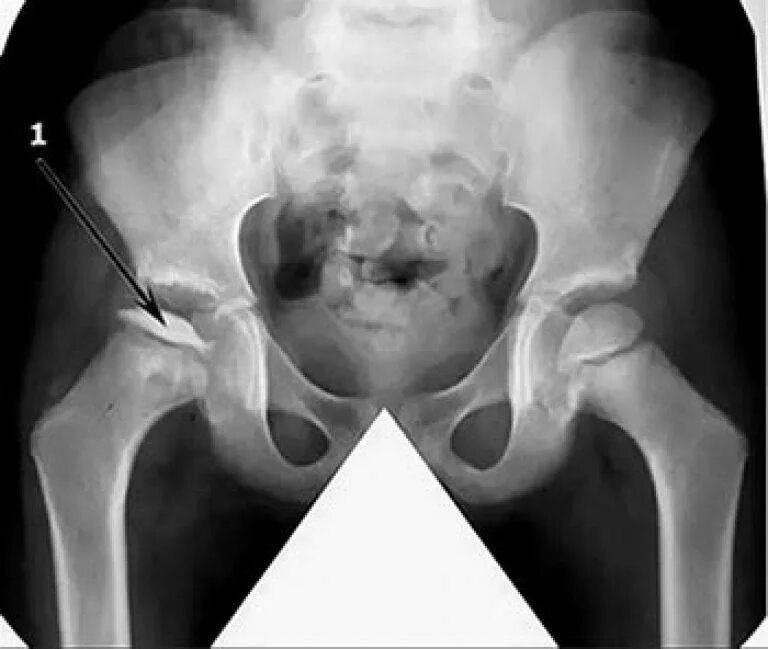

Боли при некрозе тазобедренных суставов